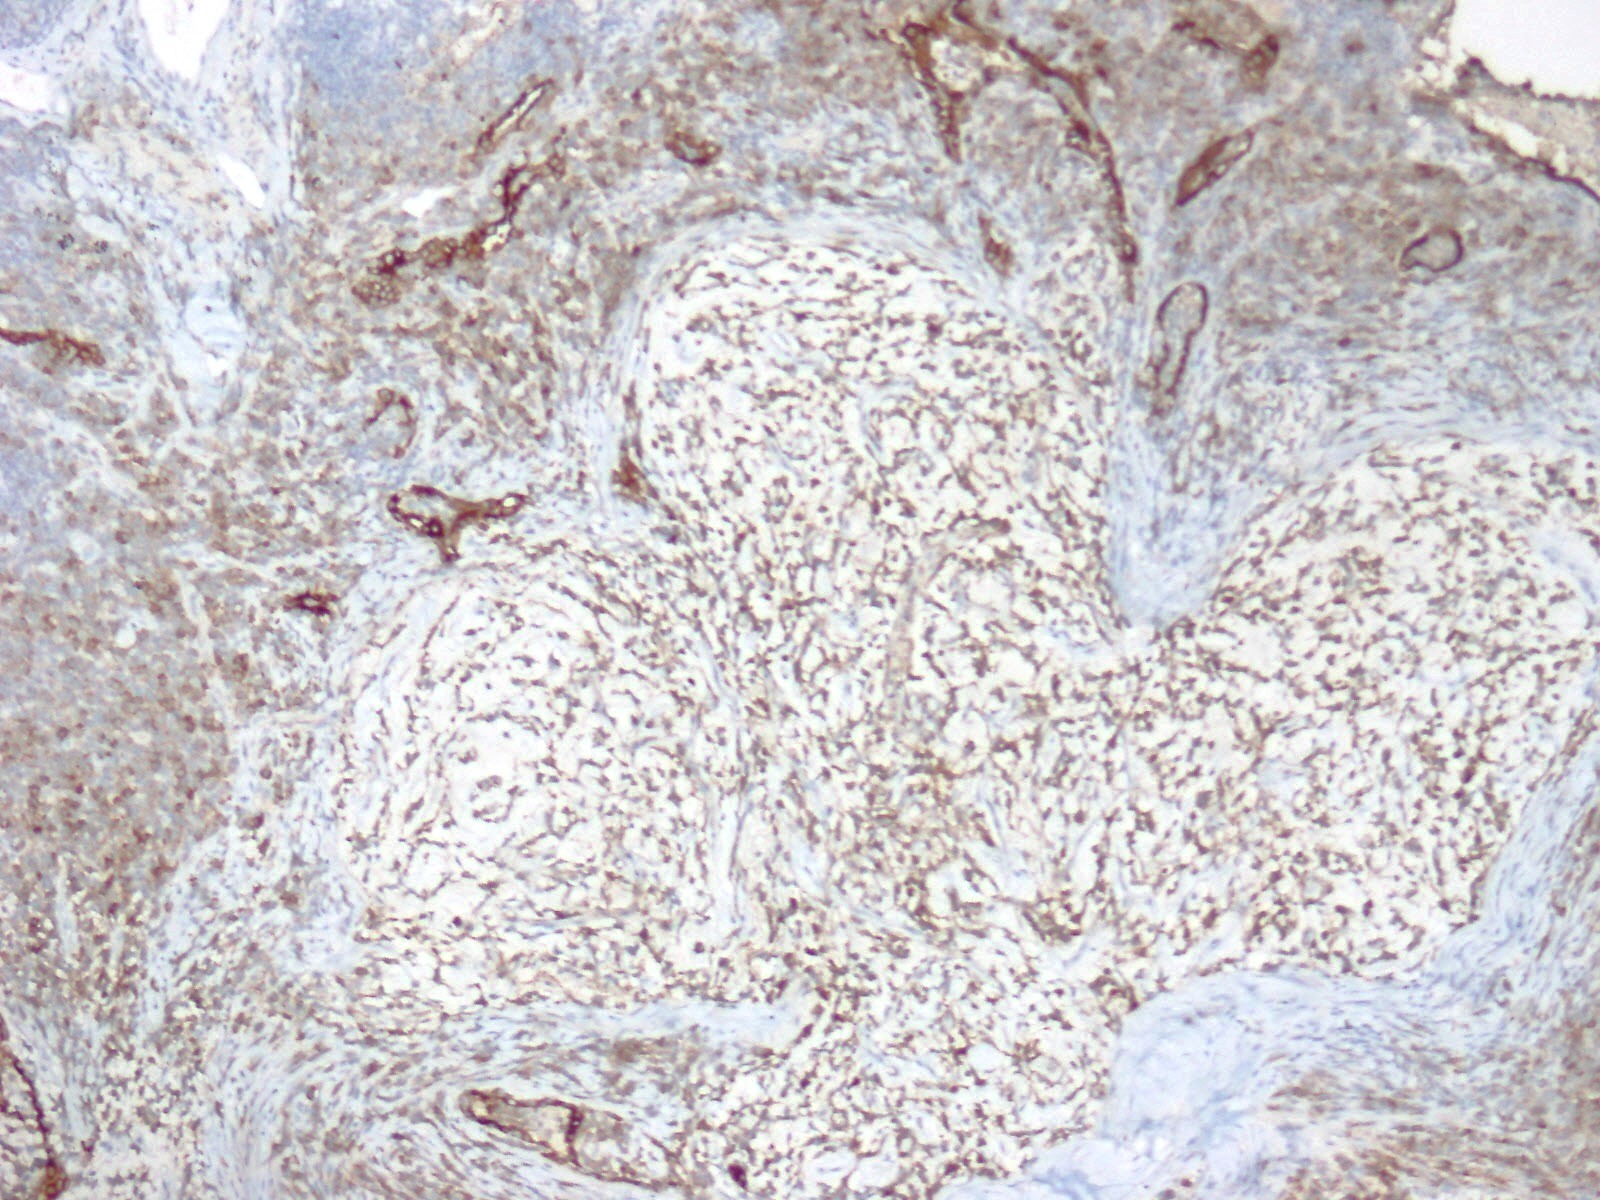

Frozen sections revealed spindle cell proliferative lesions with a rich mucoid background and a significant lymphocyte and plasma cell infiltration. It was impossible to tell if it was benign or cancerous. The tumor cells were distributed in a nodular pattern with considerable collagen interstitium, according to H&E staining. Tumor cells were spherical and oval, organized reticularly or ribbon-like in a mucoid background (Figure 2,3). Tumor cell atypia was mild to moderate. Mitotic activity was less than 2/10 HPF (high-power fields). The tumor had a mucinous background, many lymphocytes and plasma cells in the infiltrate, and many spindle cells proliferated (Figure 4).

Immunophenotypical results were negative for CK-pan, TTF-1, smooth muscle actin (SMA), S100, Desmin, CD34, CD31, and CD56; localized expression of epithelial membrane antigen (EMA) (Figure 5). The Ki67 proliferation index was low, approximately 10% (Figure 6).